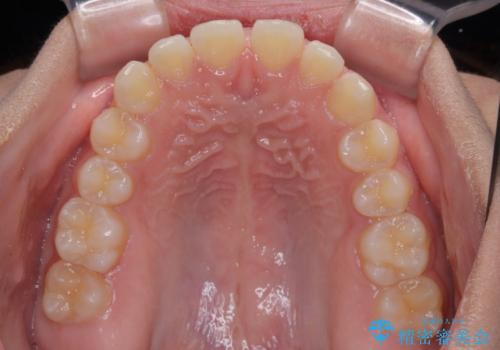

気になるすきっ歯を短期間で改善 インビザライン矯正

- 前歯の隙間を気にして来院された患者様です。

口元の突出感があり、小臼歯4本を抜歯して口元を引っ込める矯正治療も提案しましたが、本人は口元の突出感は気になっていないとのことで、インビザラインにて隙間やデコボコを改善することとしました。

軽度の歯列不正であったため、廉価版のインビザライン・モデレートパッケージにて治療を終えることができました。